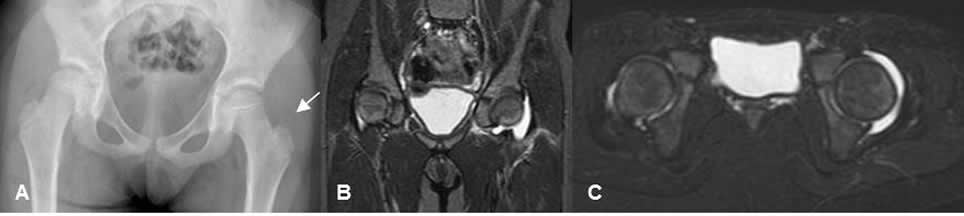

Fig 156. Derrame articular.

A: Rx AP. Desplazamiento lateral del cojinete graso glúteo, que hace sospechar derrame articular.

B: RM coronal y C: RM axial en STIR. Se confirma el derrame articular, por artritis infecciosa.